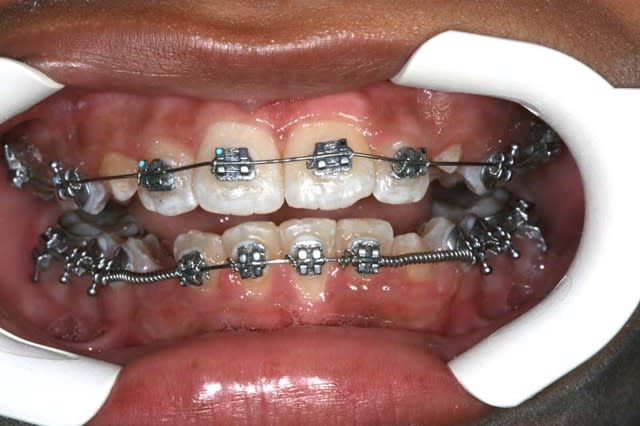

Img 1 xacnga - Eugenol

Img 2 siytdm - Eugenol

Img 3 ituagt - Eugenol

Img 4 r3tw6u - Eugenol

Img 5 z8ak0k - Eugenol